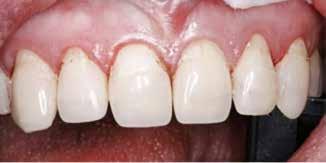

Fig. 1. A. 35-årig mand med æstetisk behov for behandling af slidte fortænder. Han skærer tænder om natten og har tidligere drukket mange læskedrikke. B og C. Incisiver og hjørnetænder er afkortede med ca. 1/4. Incisalt ses rester af plast fra tidligere plastbehandling. Al overfladestruktur i emaljen er eroderet/abraderet væk. D. Svært slid af 11 og 21 med incisal grøft, hvor dentinen er eksponeret. I den uunderstøttede incisale emalje ses chipfrakturer facialt. Lateraler og hjørnetænder har moderat slid på palatinalflader uden eksponering af dentin, men med gråligt gennemskin i slidt emalje approksimalt. E. Tæt bid og let dybt i fronten. F og G. Ingen okklusale attritionsfacetter, men let eroderet emalje på alle tyggeflader med svagt gennemskin af gullig dentin og med små cuppings på underkæbemolarer.

Fig. 1. A. 35-year-old man with aesthetic need for treatment of worn front teeth. He suffers from nocturnal bruxism and has previously been drinking many soft drinks. B and C. Incisors and canines are shortened by app. 1/4. Remnants of resin material from previous treatments are seen on the incisal edge. All surface structure in the enamel is removed by erosion/abrasion. D. Severe wear of 11 and 21 with incisal ditch where dentin is exposed. In the unsupported incisal enamel, chip fractures are seen facially. Laterals and canines have moderate wear on the palatale surfaces without dentin exposure, but with greyish gloss in worn enamel approximally. E. Close bite and slightly deep in the front. F and G. No occlusal attrition facets, but slightly eroded enamel on all chewing surfaces with a slight translucency of yellowish dentin and with small cuppings on the mandibular molars.

En ung mand på 35 år henvendte sig med et ønske om at få sine slidte fortænder gjort pænere (Fig. 1A). Han havde ingen symptomer og god funktion, men oplyste, at han skar tænder om natten. Han havde aldrig haft en bidskinne og havde flere gange tidligere fået repareret fortændernes skærekanter med plast, dog kun med kortvarig holdbarhed. Han oplyste at have haft et stort forbrug af læskedrikke gennem mange år, hvilket nu var ophørt.

Fortænder og hjørnetænder i overkæben var afkortede med ca. 1/4 (Fig. 1B, C), incisalt på 11 og 21 var der grøfter med

uunderstøttet emalje og eksponeret dentin; flere steder var der rester af plast (Fig. 1D, E). Incisiver i underkæben havde begrænset slid i emaljen. Der var let dybt bid i fronten og ved protrusion tæt kontakt mellem alle incisalkanter (Fig. 1E). I sideregionerne var der tegn på erosionsskader (små cuppings og let eroderet emalje med gulligt gennemskin af dentinen), men ikke tydelige tegn på attrition (Fig. 1F, G).

Patienten havde et æstetisk behov for behandling af det kraftige slid i fronten (attrition og erosion i forbindelse med let dybt bid), mens præmolarer og molarer med mindre okklusale erosionsskader efter ophørt erosiv påvirkning ikke havde behov for restaurerende behandling. Der var således æstetisk indikation for behandling af det anteriore tandslid.